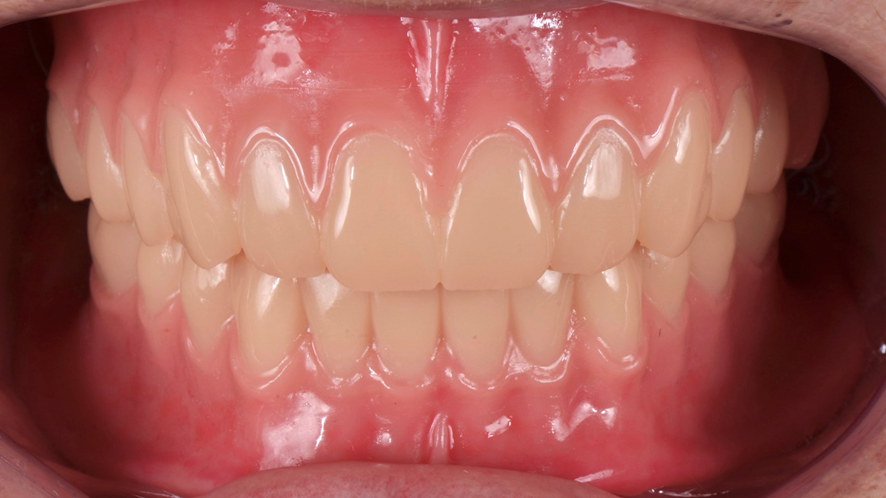

Feitas as moldagens, realizamos o escaneamento 360o das próteses, oclusão e escaneamento dos lábios (Figura 12). Então, enviamos os arquivos ao laboratório de prótese para confecção das próteses totais digitais (Figura 13). Após aprovado os desenhos, recebemos as próteses totais impressas e maquiadas para fazer a captura das cápsulas dos O’rings.

Use uma resina acrílica para capturar as cápsulas metálicas. Coloque a resina acrílica nas cápsulas metálicas e nas perfurações na base da prótese (Figura 16) e assente a prótese sobre as cápsulas metálicas e o rebordo alveolar. Instrua o paciente a ocluir e manter a posição até a resina polimerizar. Após a polimerização da resina, faça o acabamento e polimento na região das cápsulas (Figura 17) e encaixe a prótese total nos componentes O’ring (Figura 18).